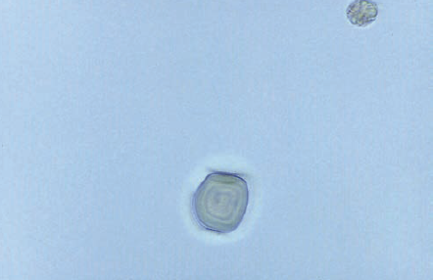

| Pollen granule ( notice the concentric circles) | |